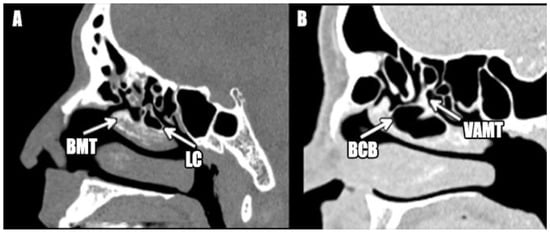

Figure 2.

Bulbous and lamellar concha bullosa: (A): Lamellar concha bullosa. Note that the cell is only lamellar cell (LC) and is not affecting the body of the middle turbinate (BMT). (B): Bulbous concha bullosa (BCB). Note that the cell is not affecting the vertical aspect of the middle turbinate (VAMT).